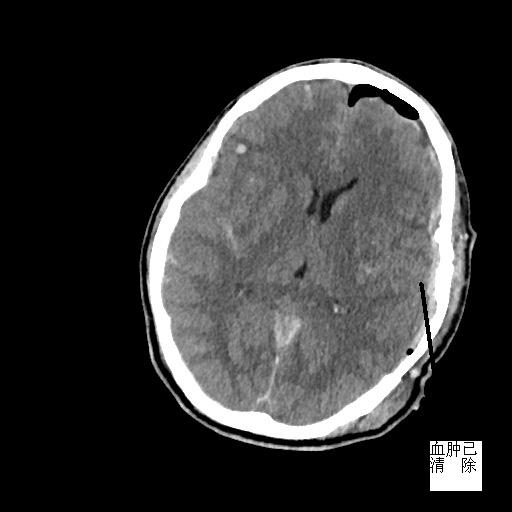

患者潘先生,因騎車(chē)摔倒入院搶救。入院時(shí),潘先生神志已模糊,無(wú)法對(duì)答,經(jīng)相關(guān)檢驗(yàn)檢查,提示顱內(nèi)多發(fā)損傷,我院神經(jīng)外科MDT團(tuán)隊(duì)緊急會(huì)診,評(píng)估病情,并給予緊急處理。潘先生情況不容樂(lè)觀,顱內(nèi)壓明顯增加,出現(xiàn)腦疝,若不緊急手術(shù),顱內(nèi)壓可進(jìn)一步增加,到時(shí)將造成不可逆腦損傷,甚至危及生命。家屬了解到我院與福醫(yī)大附二院建立神經(jīng)外科專(zhuān)科聯(lián)盟,每天有專(zhuān)家值班在線指導(dǎo),可緊急來(lái)院幫扶搶救,遂放棄轉(zhuǎn)院,決定入院治療。

接到信息,當(dāng)日值班專(zhuān)家黃金鐘主任立即趕來(lái)。為與病魔賽跑,黃主任爭(zhēng)分奪秒利用途中時(shí)間,在了解潘先生病情的基礎(chǔ)上與我院專(zhuān)家討論病情、評(píng)估手術(shù)相關(guān)風(fēng)險(xiǎn)、確定手術(shù)方案……同時(shí),我院神經(jīng)外科完善術(shù)前檢查、備血、剃頭等術(shù)前準(zhǔn)備,確保專(zhuān)家到位后,潘先生能第一時(shí)間送入手術(shù)室。

經(jīng)黃主任與我院專(zhuān)家合力搶救,潘先生手術(shù)順利,轉(zhuǎn)入ICU進(jìn)一步治療。術(shù)后,潘先生意識(shí)逐漸清醒,目前在福醫(yī)大附二院神經(jīng)外科專(zhuān)家參與下進(jìn)行后續(xù)康復(fù)治療。